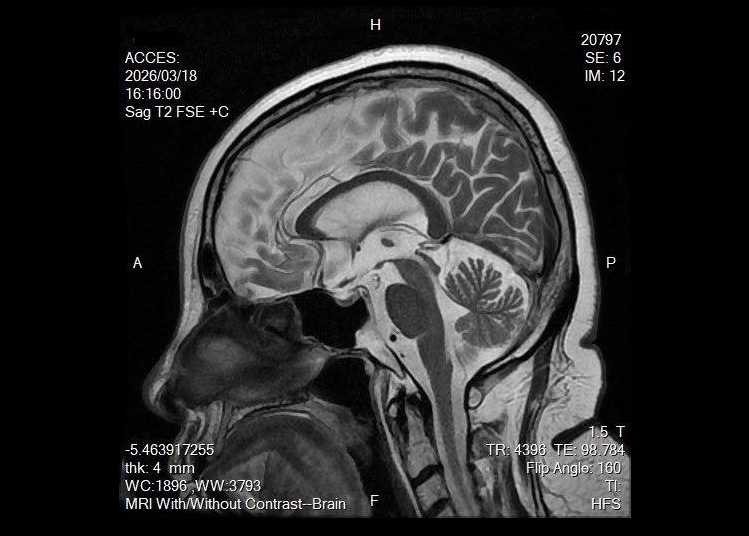

資深媒體人陳文茜即將於3月25日迎來68歲生日,罹患黑色素癌的她,經常透過社群分享抗癌過程和心情,在生日前夕她突然感性發文,詳述與黑色素癌及多種罕見疾病搏鬥的心路歷程,並將這場大病視為「生命送給她的禮物」,同時親揭在台大癌醫中心的最新檢查結果,目前腦部相當乾淨、未見癌細胞擴散,令長期抗癌的她忍不住讚嘆,「終究沒有辜負自己」。

由於陳文茜身上患有多種罕見疾病且腫瘤形狀特殊,連主治醫師都戲稱她是構造獨特的「外星人」;在生日前夕令她驚喜的是,追蹤腦癌結果顯示,腦部乾乾淨淨,沒有癌細胞,沒有「世俗的雜物」。而陳文茜與占星學家好友林靜宜對話時,更幽默表示若未來離開人世,歸宿將是象徵死亡與重生的「冥王星」。